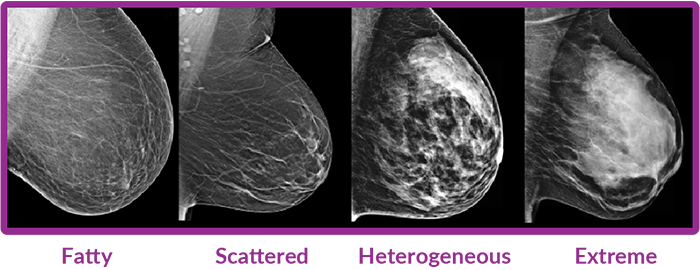

What is Breast Density?

Breast density is the amount of glandular and connective tissue compared to fatty tissue in your breasts. Dense breasts can make it harder for mammograms to detect tumors.

- Cancers can be more challenging to detect in dense breast tissue as tissue and tumors appear white on mammograms1.